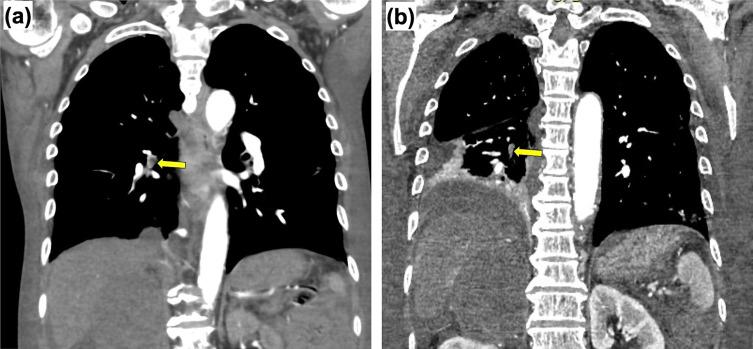

A 78-year-old Japanese man presented to the emergency department with a sore throat and fever that worsened over 3 weeks. A tonsil biopsy led to the diagnosis of pleomorphic mantle cell lymphoma (MCL) that had infiltrated the right adrenal gland, inferior vena cava, and right atrium (RA). Although the patient's cardiac tumor had high mobility, his hemodynamic state was stable, and he did not present with fatal arrhythmia. Therefore, we first introduced chemotherapy. However, the patient developed recurrent pulmonary embolisms (PEs) and died after starting chemotherapy. An autopsy revealed that the MCL had invaded the large vessels, causing the PEs. Although the high mobility of cardiac tumors is known to increase the risk of PE in diffuse large B-cell lymphoma (DLBCL), optimal management of cardiac MCL remains to be elucidated owing to its rarity. To the best of our knowledge, this is the first report of cardiac MCL with posttreatment PE development in a Japanese patient. It is worth considering preventive surgery before treatment not only in DLBCL, but also in MCL based on the mobility of the cardiac tumors. Our case highlights the need for close communication between hematologists and cardiologists to treat cardiac MCL.

一位 78 岁的日本男性因喉咙痛和发热就诊于急诊科,这些症状在 3 周内逐渐加重。扁桃体活检提示多形性套细胞淋巴瘤(MCL)浸润右侧肾上腺、下腔静脉和右心房(RA)。尽管患者的心脏肿瘤活动度高,但他的血流动力学状态稳定,也没有出现致命性心律失常。因此,我们首先引入了化疗。然而,患者开始化疗后反复发生肺栓塞(PE)并死亡。尸检显示 MCL 侵犯了大血管,导致了 PEs。尽管已知弥漫性大 B 细胞淋巴瘤(DLBCL)中心脏肿瘤的高活动度会增加 PE 的风险,但由于其罕见性,心脏 MCL 的最佳治疗管理仍有待阐明。据我们所知,这是首例日本患者在治疗后发生心脏 MCL 伴 PE 发展的报告。不仅在 DLBCL 中,而且在基于心脏肿瘤活动度的 MCL 中,在治疗前都值得考虑预防性手术。我们的病例强调了血液科医生和心脏病专家之间需要密切沟通来治疗心脏 MCL。